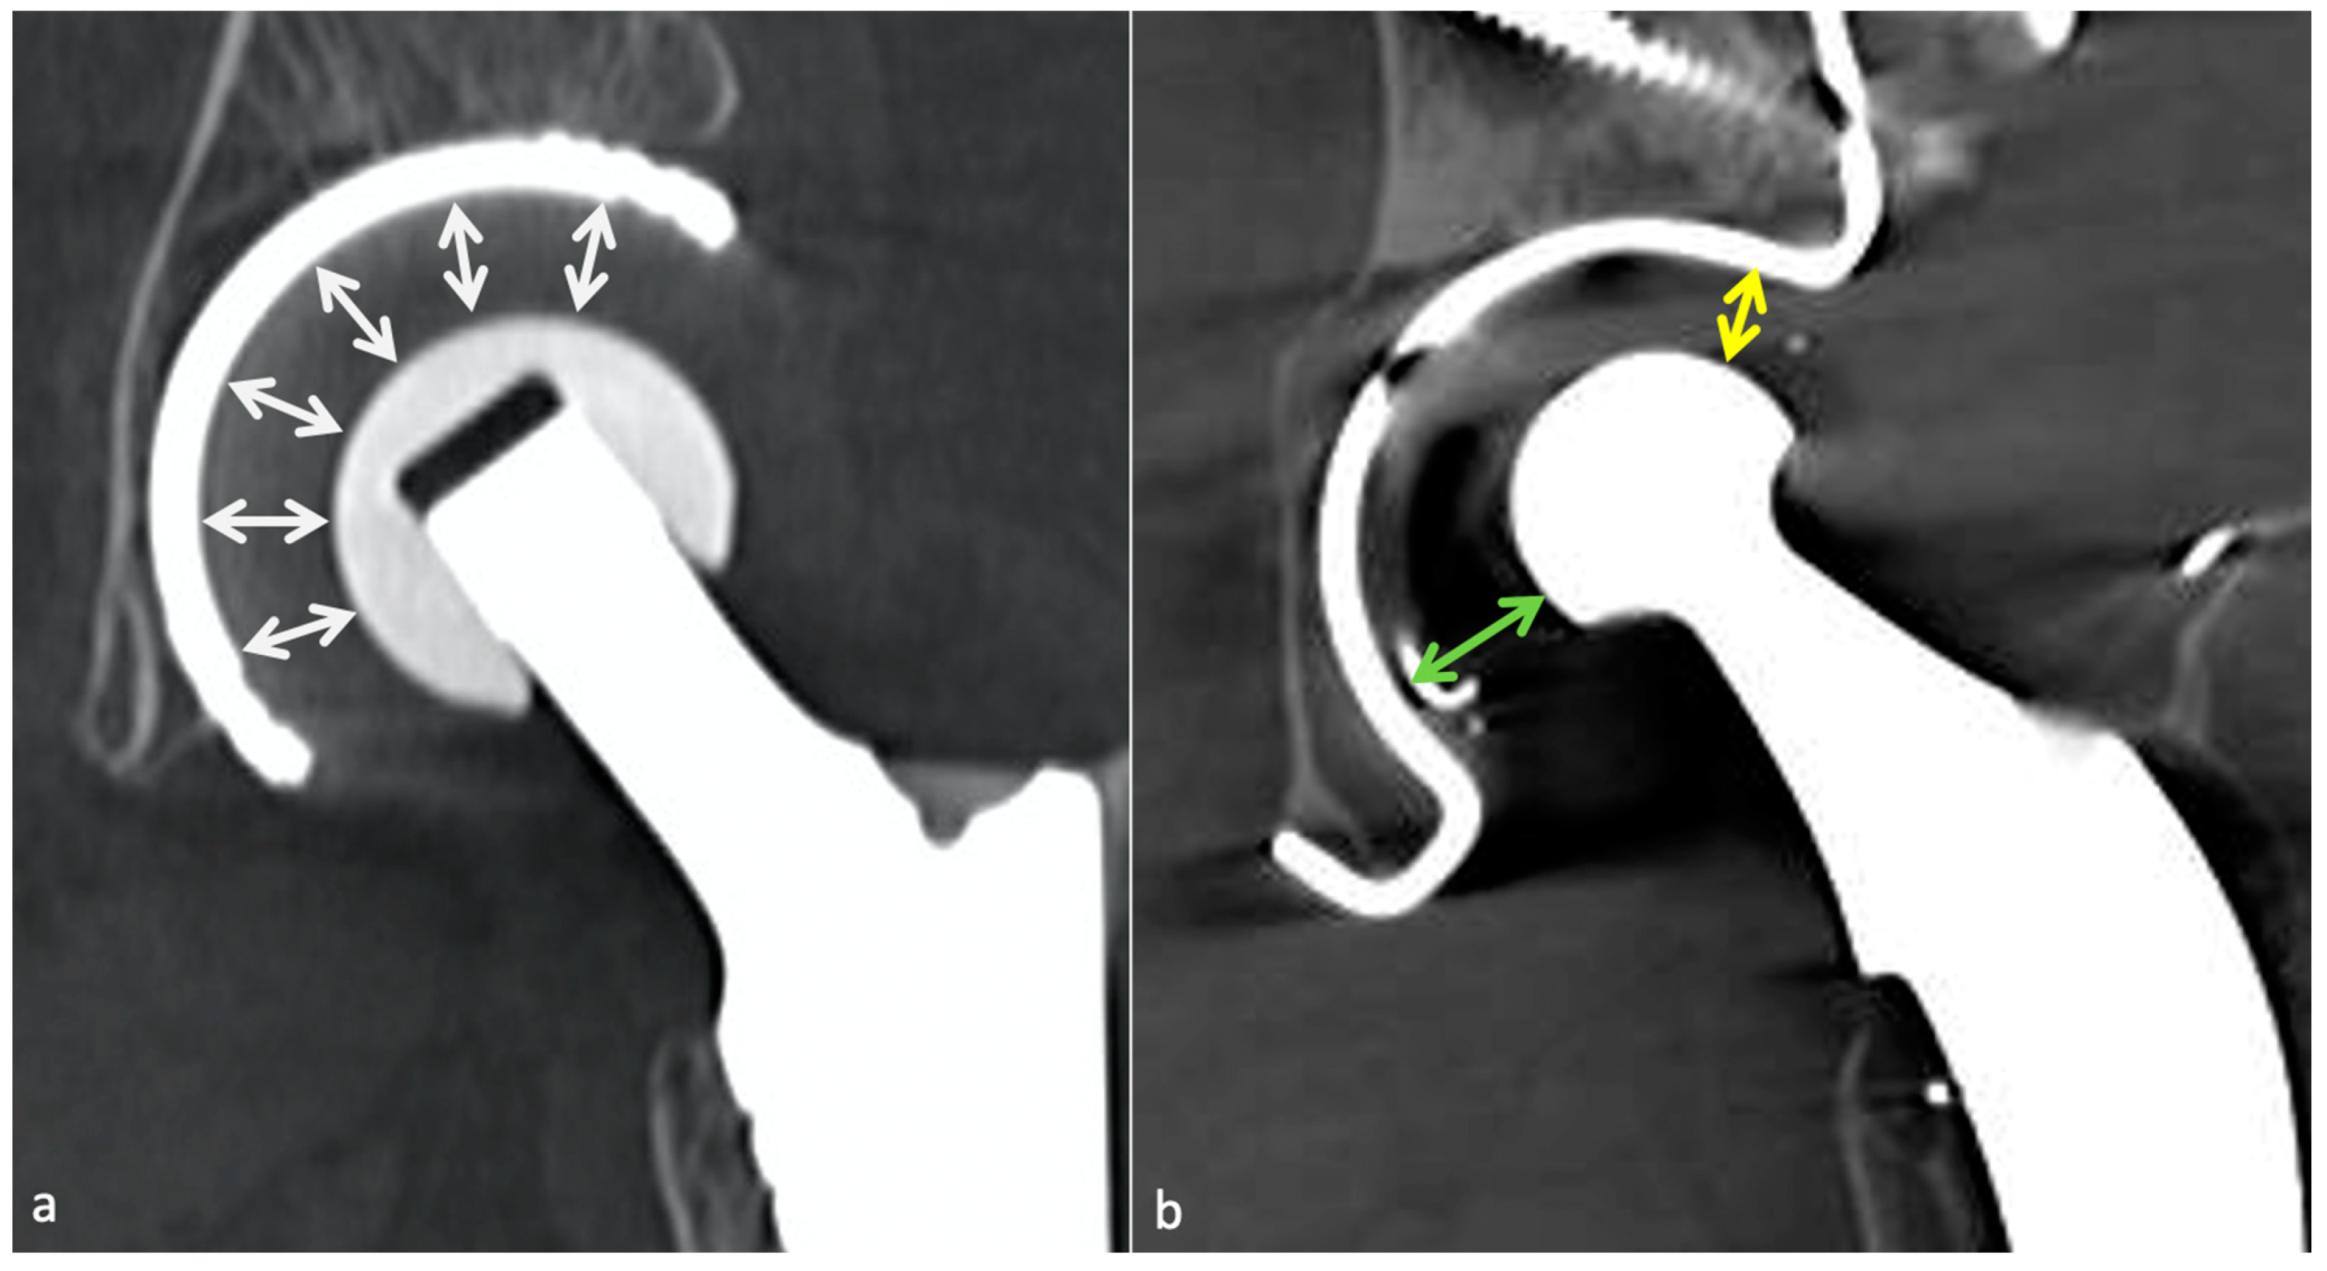

4.5.2. Classification and Contribution of Imaging Methods

- Metallosis results from the shedding of metallic debris (secondary to a MoM prosthesis with corrosion, a conflict between a metallic acetabular cup and the prosthetic neck, or a contact between a metallic head and an acetabular metal back in case of PE wear or dislocation) that induces synovitis and an indolent pattern of osteolysis, potentially leading to loosening (i.e., potentially looking similar to osteolysis and PE wear). Synovitis may contain low-signal intensity or metallic density debris, causing MRI artifacts and bone erosion, best depicted on CT-MAR (Figure 20). Such debris might also be located in periprosthetic soft tissue and lymph nodes [54,57]. Metallic debris presence might also accentuate PE wear (i.e., third fragment wear) [54]. Of note, high serum metal-ion levels can be found in symptomatic and asymptomatic patients and would be associated with pseudo-tumors, so that such a biological finding should lead to the prescription of an MRI to rule out a pseudo-tumor even in asymptomatic patients [6,103].

- Additionally, referred to as trunnionosis, trunnion corrosion corresponds to a soft-tissue reaction to metal debris released from micromotion and mechanical wear at the head–neck or neck–stem junction of modular MoP HA. On MRI, it manifests as an adverse local reaction associated with medial calcar resorption [11,104].

4.5.3. MRI Focus